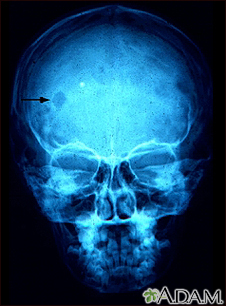

Eosinophilic granuloma - x-ray of the skull